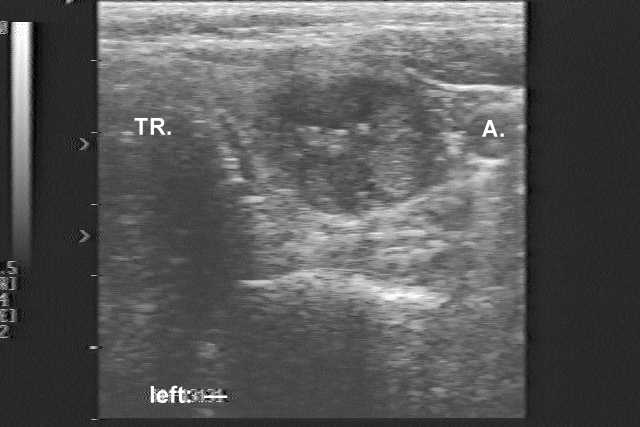

Ultrasonography. There was a hypoechogenic nodule in the left lobe with patchy hyperechogenic areas and microcalcifications.

Comment. This was our first case of medullary cancer. Naturally, our first cytological diagnosis was false. We had to raise the possibility of a medullary carcinoma even at the first examination. The sonographic pictures are out of date, nevertheless the pathognomonic pattern of medullary carcinoma is well seen on these old images, as well.